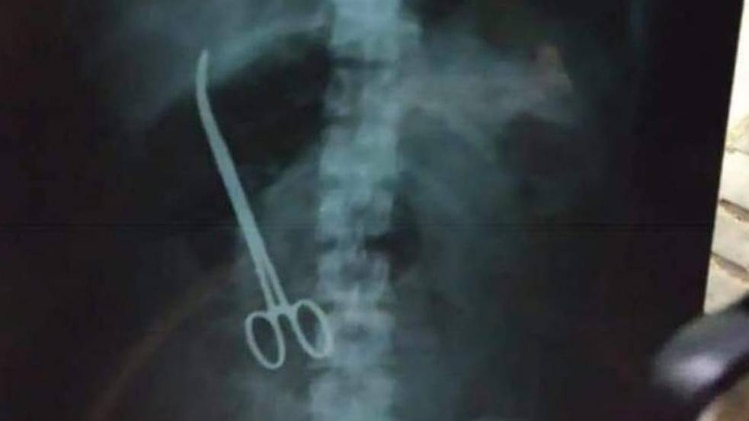

पीड़िता का कहना है कि 2023 से 2025 के बीच इलाज के नाम पर करीब 5 लाख रुपये ले लिए गए. परेशानी बढ़ने पर 2 अगस्त 2025 को एरा अस्पताल में अल्ट्रासाउंड कराया गया, जिसके बाद डॉक्टरों ने एपेंडिसाइटिस बताकर तुरंत ऑपरेशन और फीस जमा करने को कहा. संदेह होने पर पीड़िता ने 8-9 अगस्त 2025 को चरक अस्पताल में सीटी स्कैन कराया, जिसमें पेट के अंदर सर्जिकल औजार होने की पुष्टि हुई.

20 अगस्त 2025 को चरक अस्पताल में ऑपरेशन कर पेट से सर्जिकल औजार निकाला गया. डिस्चार्ज समरी में इसका स्पष्ट ब्योरा है. ऑपरेशन के बाद पीड़िता की हालत बिगड़ने पर उन्हें आईसीयू में भर्ती करना पड़ा.